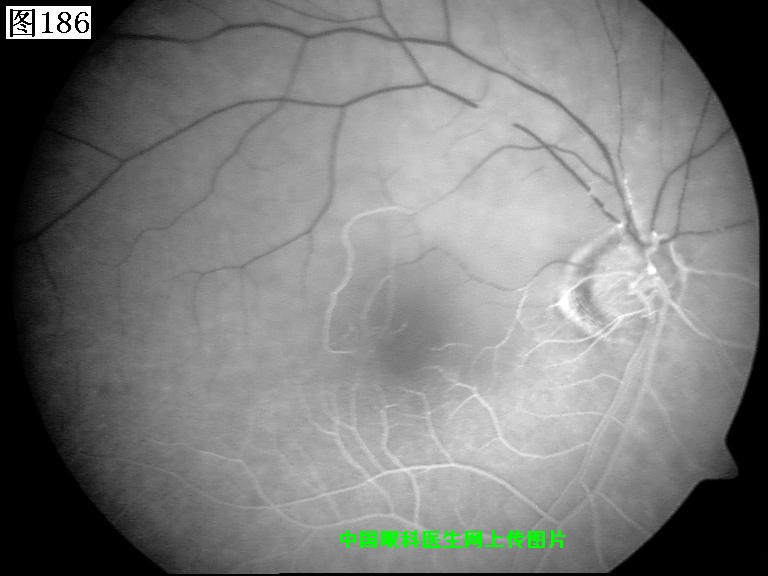

185 186 187 188